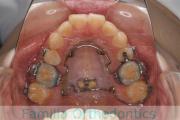

横顔が気になるとのことで来院されました。叢生(でこぼこ、凹凸、ガタガタ)を伴う上下顎前突(口元が出ていること)を呈しているため、上下左右から小臼歯を抜歯して歯科矯正用アンカースクリューとマルチブラケットにより2年弱の治療を行いました。

上顎

下顎